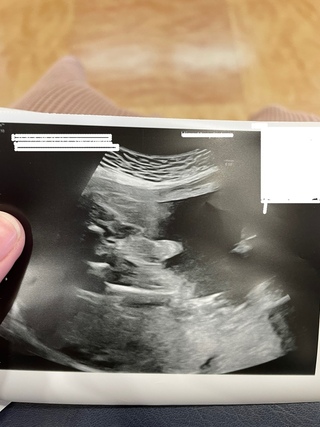

妊娠26週6日(26w6d)の赤ちゃんのエコー写真です。投稿も募集しています。 27週目に入る前のハーフベビーです。 先生から顔が濃いね、とのことですが、同じ頃の日本人ベビーとあまり変わらないような気がします。 初めて顔を拝見しました。妊娠26週目エコー写真で見る胎児の体重と大きさ・早産になったら 妊娠26週目(26w)のエコー写真を見ると、胎児の大きさはCRL(頭殿長)は36cm、体重は750~1000gほどに成長。 脳は新生児と似たものに近づく時期。 妊娠二十六週での万が一の出産は早産となり、新生児治療の対象となる週数です。 母体は妊娠性ホルモンの影響で糖尿傾向になります。 執筆者:竹内妊娠26週目に入りました。 7ヶ月26週0日 1日目ですね。 出産予定日まではあと98日です。 この頃の赤ちゃんは 身長は34~37cm 体重は750~1,000gくらいです。 妊婦健診のたびに我が子の様子をエコー画像で見てます。 成長が分かって楽しいですよ。

妊娠26週6日(26w6d)の赤ちゃんのエコー写真です。投稿も募集しています。 27週目に入る前のハーフベビーです。 先生から顔が濃いね、とのことですが、同じ頃の日本人ベビーとあまり変わらないような気がします。 初めて顔を拝見しました。妊娠26週目の赤ちゃんの大きさは? 妊娠26週目の赤ちゃんの大きさはズッキーニぐらいです。 妊娠26週目の赤ちゃんの頭からお尻までの平均身長は23センチメートルほど、平均体重は900グラムほどです。 妊娠26週目のママの体ママはお腹がふくらみ、赤ちゃんは1kgを超えるくらいに 妊娠26週になると子宮底長は24cm~30cmほどになり、子宮のてっぺんはおへそより上にきます。 お腹の下側だけでなくウエストのあたりまで膨らんできます。 お腹も目立つようになり、それに伴い腰痛や寝苦しさが出てくる妊婦さんもいるかもしれません。 出典: featurecozrejp 個人差はありますが、だいぶお腹